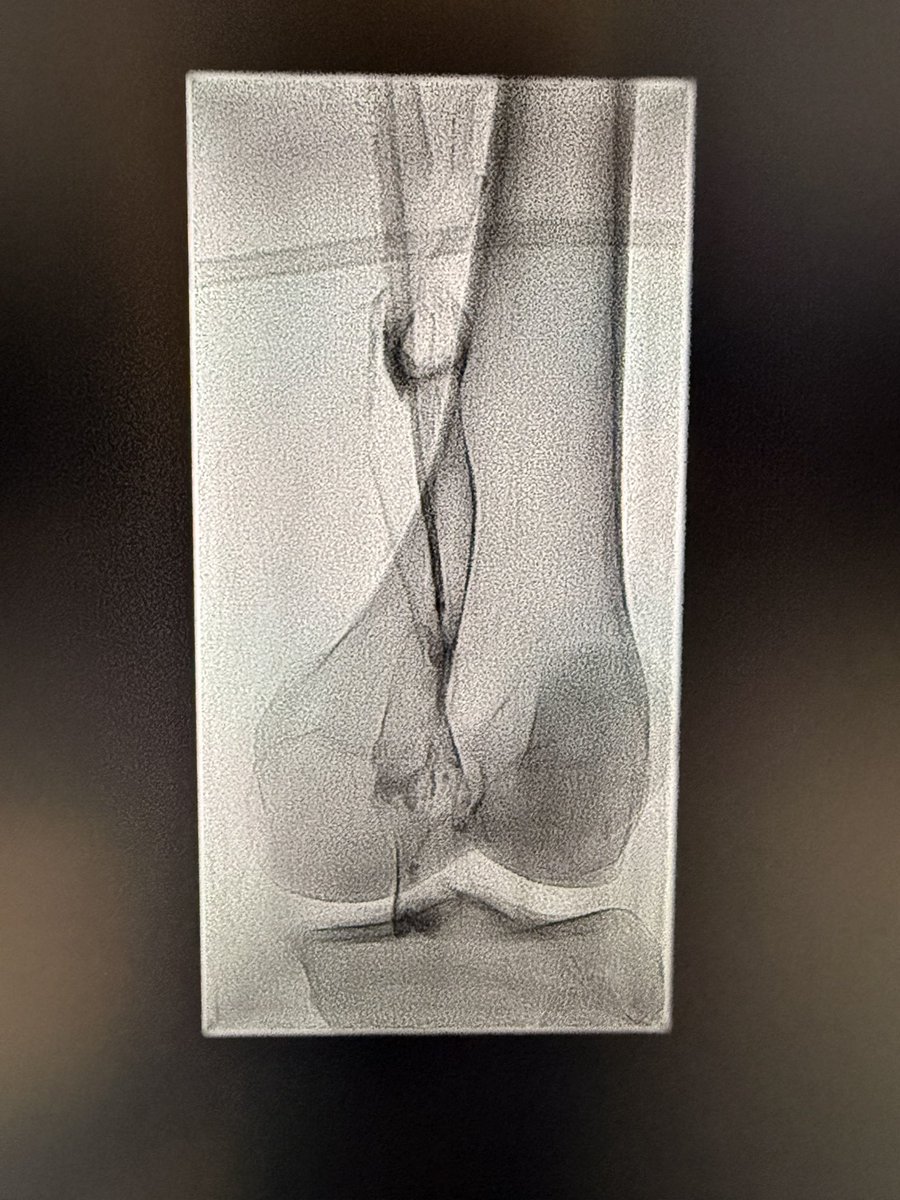

An estimated 30 million Americans — or more than 11 percent of the adult population — suffer from knee osteoarthritis, the degenerative disease that prompts most knee replacements. For those who don’t want to undergo the surgery, other options exist. wapo.st/4kdVLxe